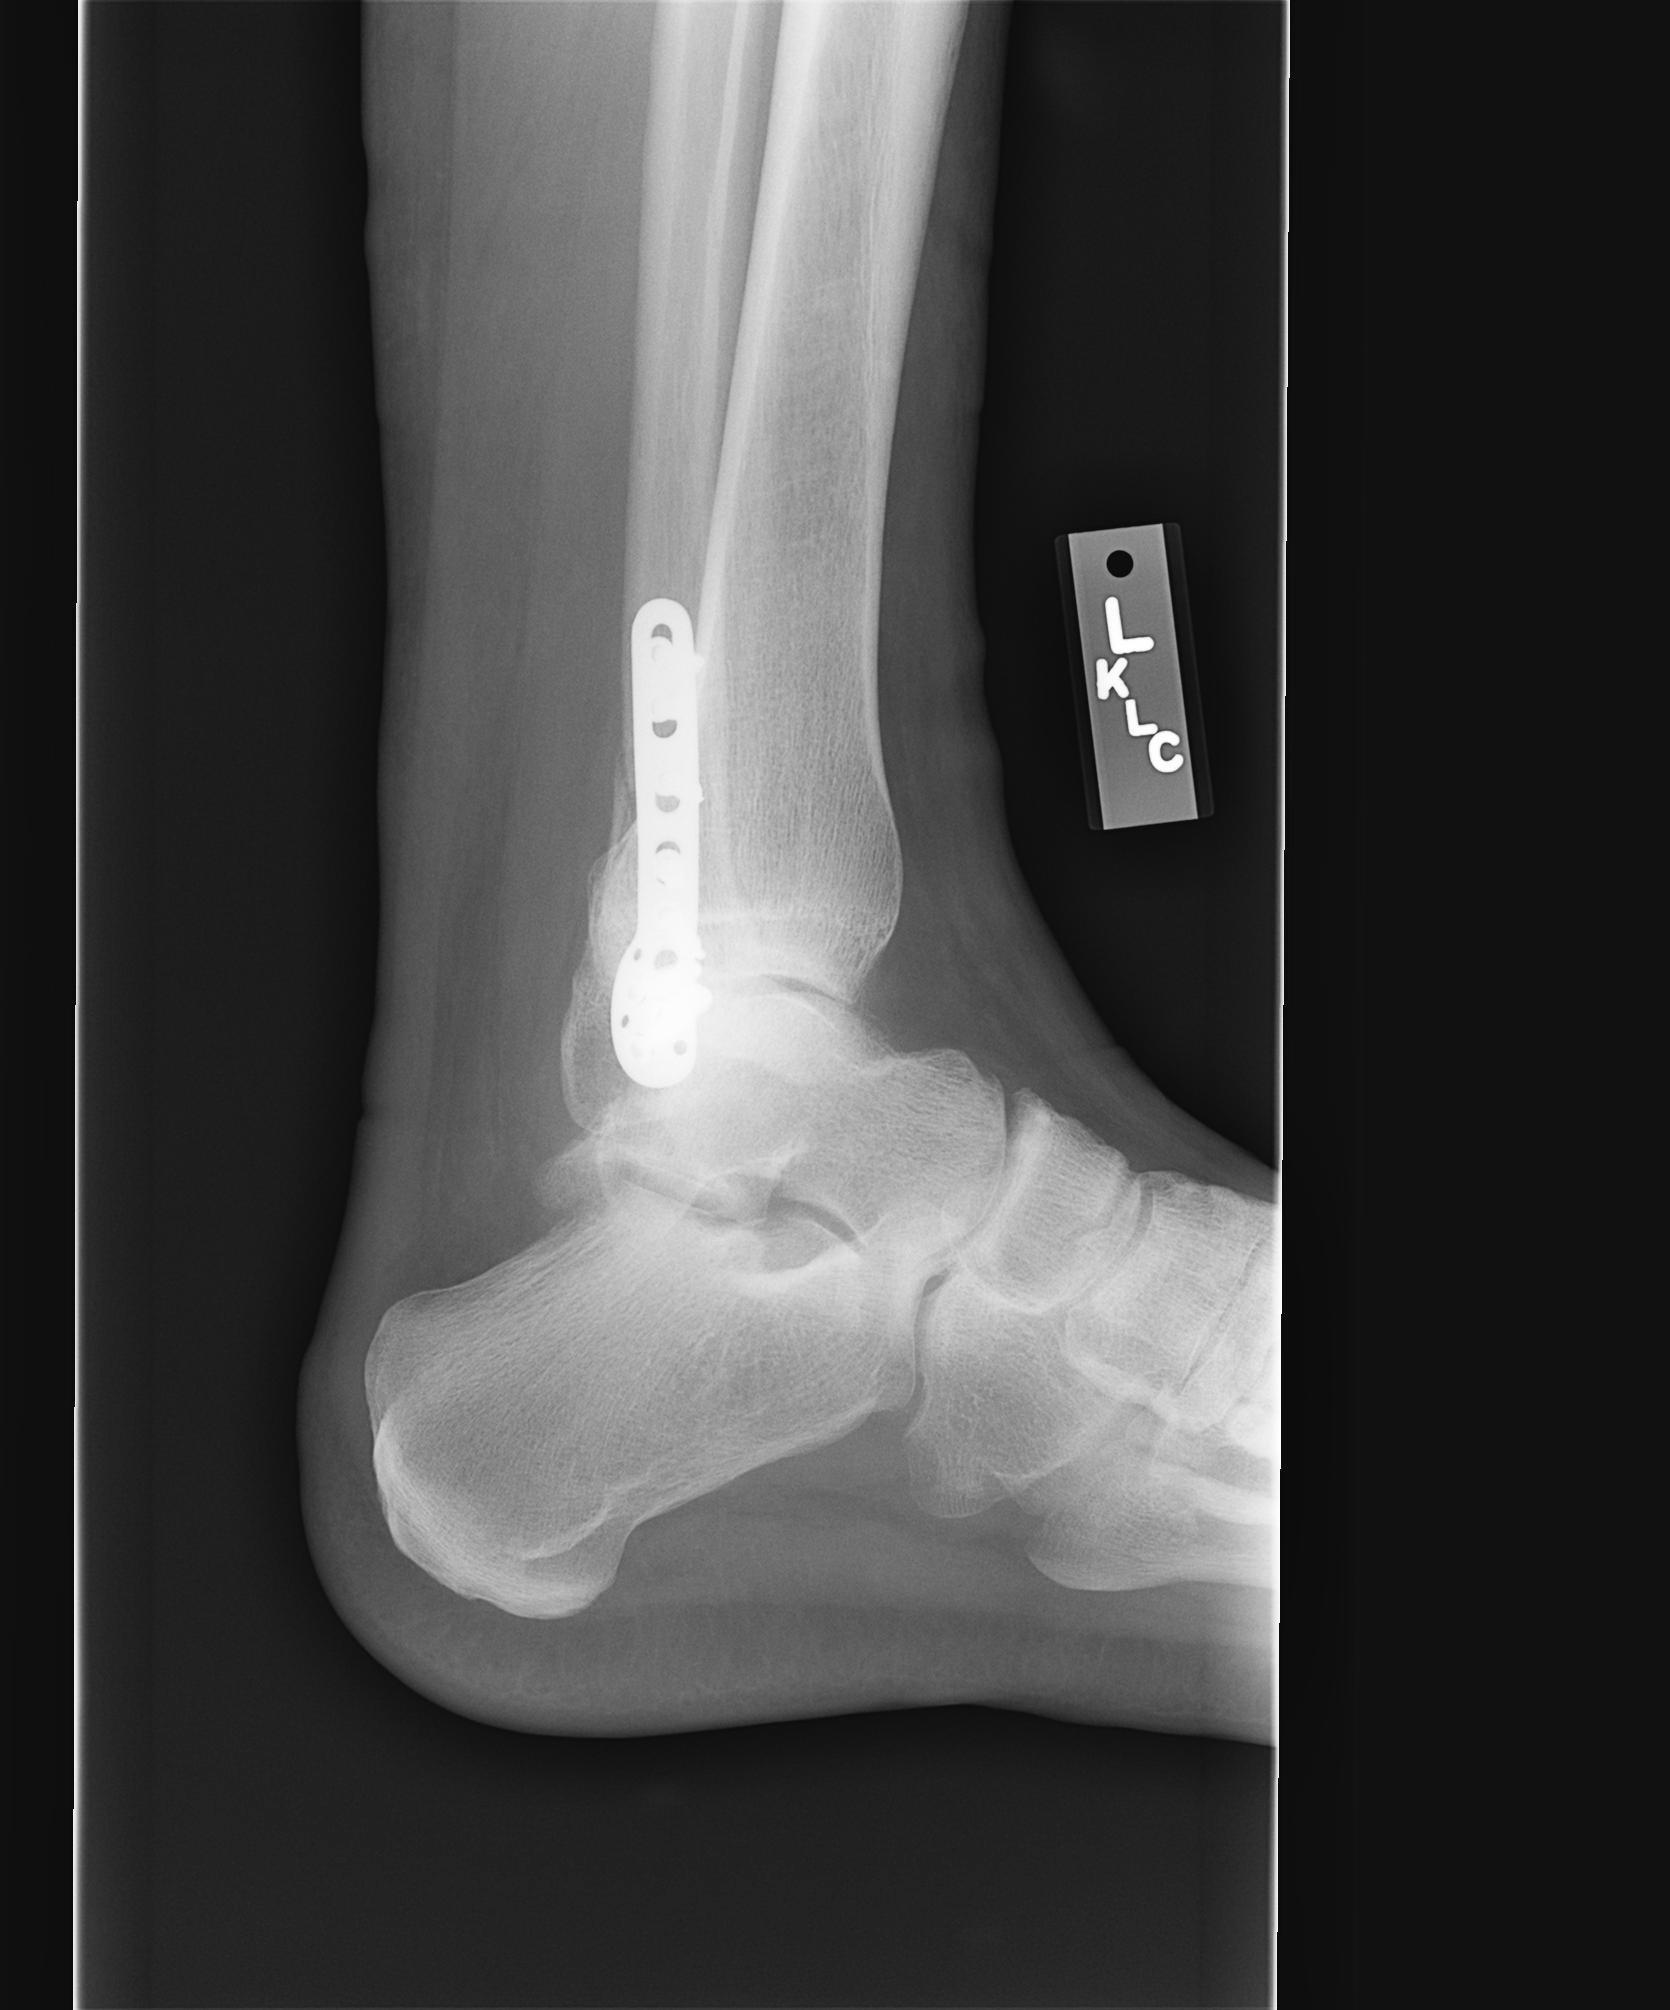

7-17-07

Dr. Visit 8-8-07 - The infection is healing and x-rays show most of the fracture has filled in. Look mid plate and to the left on x-ray #3 to see what is left of the fracture.